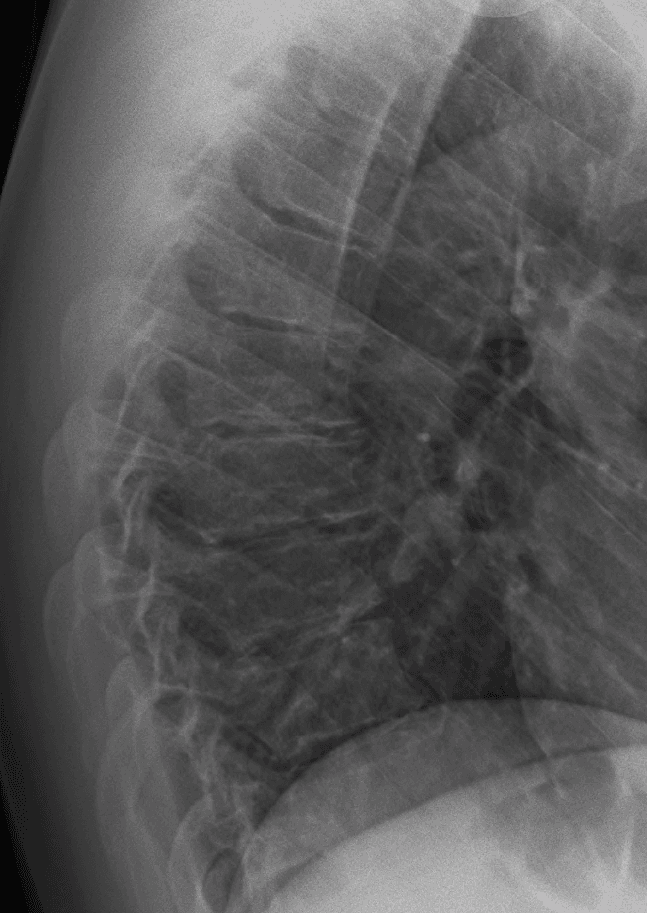

Scheuermann's disease is a self-limiting skeletal disorder of childhood. Scheuermann's disease describes a condition where the vertebrae grow unevenly with respect to the sagittal plane; that is, the posterior angle is often greater than the anterior. This uneven growth results in the signature "wedging" shape of the vertebrae, causing kyphosis. It is named after Danish surgeon Holger Scheuermann. Scheuermann's disease is considered to be a form of juvenile osteochondrosis of the spine. It is found mostly in teenagers and presents a significantly worse deformity than postural kyphosis. Patients suffering with Scheuermann’s kyphosis cannot consciously correct their posture. The apex of their curve, located in the thoracic vertebrae, is quite rigid. Scheuermann's disease is notorious for causing lower and mid-level back and neck pain, which can be severe and disabling. The sufferer may feel pain at the apex of the curve, which is aggravated by physical activity and by periods of standing or sitting; this can have a significantly detrimental effect to their lives as their level of activity is curbed by their disability. The sufferer may feel isolated or uneasy amongst their peers if they are children, depending on the level of deformity. In addition to the pain associated with Scheuermann's disease, many sufferers of the disorder have loss of vertebral height, and depending on where the apex of the curve is, may have a visual 'hunchback' or 'roundback'. It has been reported that curves in the lower thoracic region cause more pain, whereas curves in the upper region present a more visual deformity. Nevertheless, it is typically pain or cosmetic reasons that prompt sufferers to seek help for their condition. In studies, kyphosis is better characterized for the thoracic spine than for the lumbar spine. The seventh and tenth thoracic vertebrae are most commonly affected. It causes backache and spinal curvature. In very serious cases it may cause internal problems and spinal cord damage, but these cases are extremely rare.